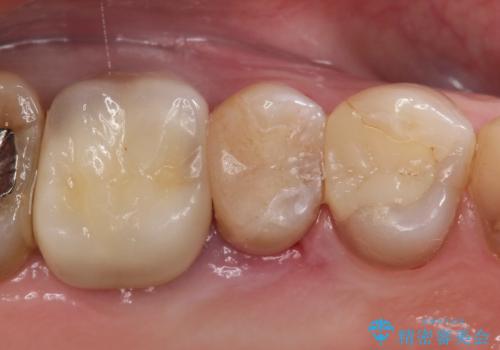

[ 深い虫歯・根管治療・セラミッククラウン ]複合した問題を持った虫歯治療

![[ 深い虫歯・根管治療・セラミッククラウン ]複合した問題を持った虫歯治療の症例 治療前](https://seimitsushinbi.jp/wp/wp-content/uploads/2022/09/b464b4c5c3053a5fc84212fb664a039f-500x350.jpg?v=1663667230)

![[ 深い虫歯・根管治療・セラミッククラウン ]複合した問題を持った虫歯治療の症例 治療後](https://seimitsushinbi.jp/wp/wp-content/uploads/2022/09/bd017e5dbd742f9bb33f09d39c8f1b52-500x350.jpg?v=1663667487)